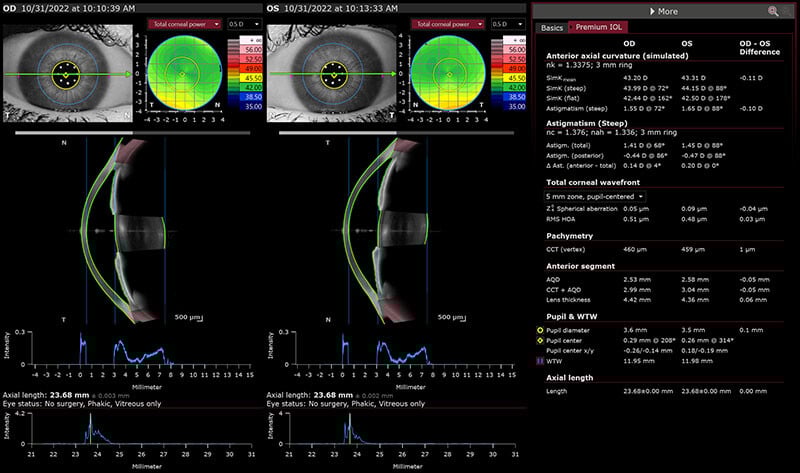

Biometry OU View with Premium IOL data

The ANTERION – based on advanced SS-OCT technology - can help to prevent unexpected results by identifying complex ocular properties relating to anatomy, visual quality, and atypical geometry of the eye. In a single imaging session, via the Cataract App, ANTERION can provide accurate measurements traditionally provided by several devices including axial length, keratometry, anterior chamber depth, lens thickness, white-to-white, and central corneal thickness. These are presented in an order that can aid IOL power predictions and decision making. For many surgeons the corneal wavefront element is a major factor in discussions about advanced technology IOLs -